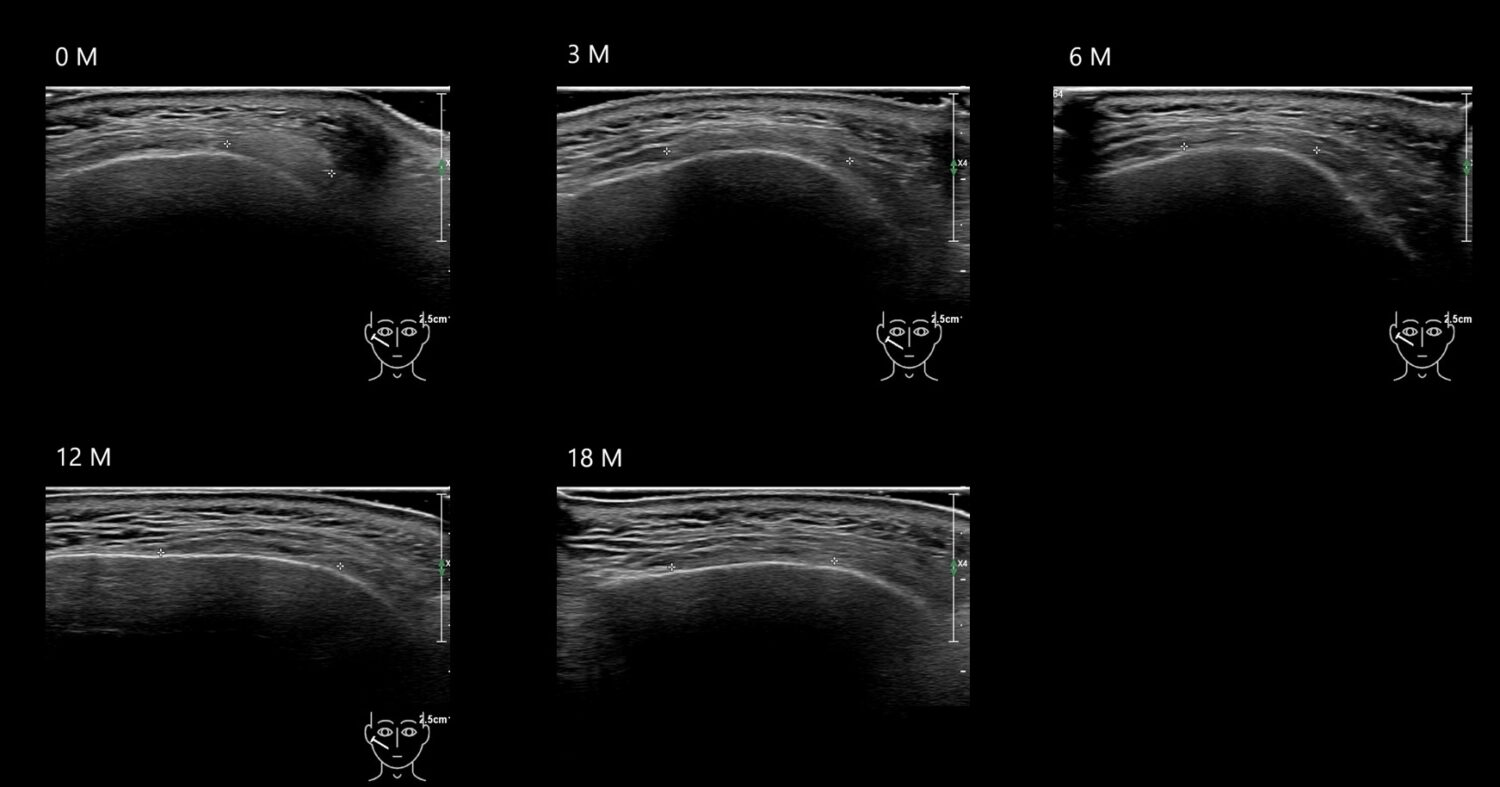

Fillers

Draw in the image on the right where the fillers are located. To check if your answer is correct, please click on the secondary image.